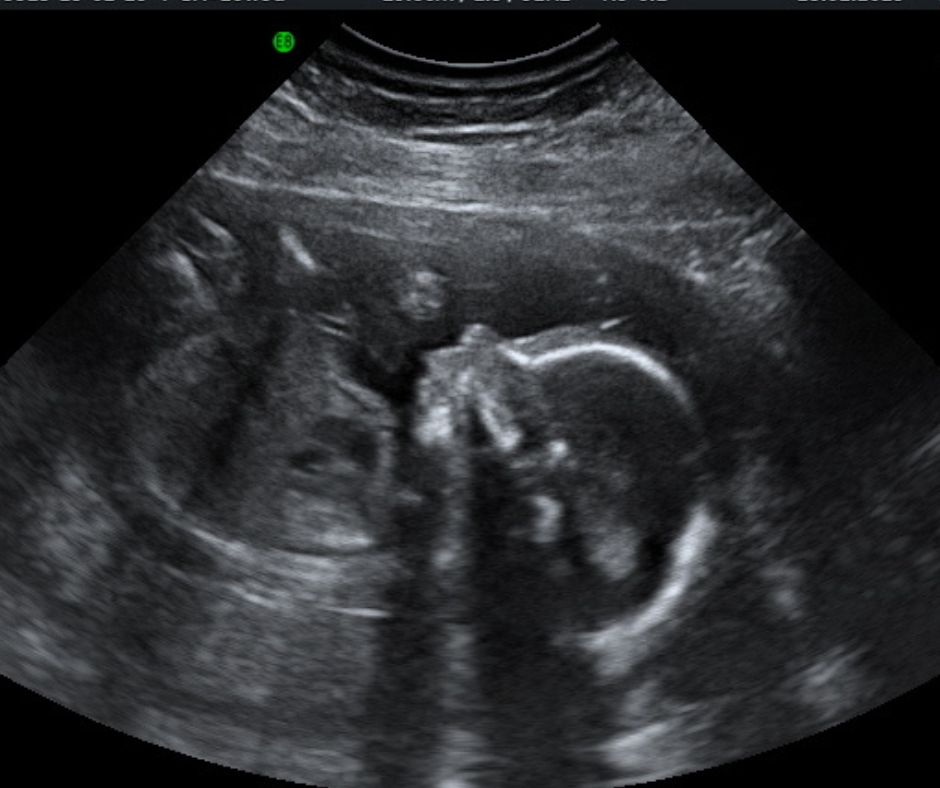

2D Reassurance Scans

One of the great benefits of ultrasound is the possibility of reassuring you that your pregnancy is running smoothly.

2D Reassurance scan this is to check the well being of your baby

This scan is available from at least 18 weeks to no more than 24 weeks, is designed to give you a reassurance it include:

The quality of the visual result of the scan is dependent on the stage of pregnancy, the size and position of the baby, the volume of amniotic fluid and the amount of tissue (skin, muscle, etc) between the ultrasound probe and the foetus in the womb. A good image cannot always be obtained.